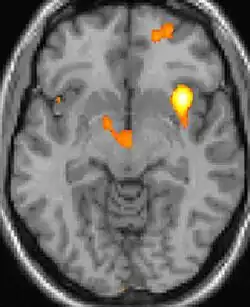

![]() |

| Tomografia PET mostrando áreas ativadas na dor. | ||

| VBM mostrando diferenças estruturais entre cérebros | ||

As reais causas da cefaleia em salvas (CES) ainda são desconhecidas, mas, de acordo com alguns estudos, os padrões das crises, as influências pelo horário do dia e as estações sugerem que o relógio biológico do corpo está envolvido. Nos seres humanos, o relógio biológico está situado no hipotálamo. Durante um ataque, o hipotálamo libera substâncias químicas que podem estimular as células nervosas no cérebro, causando dor e outros sintomas. A hiperatividade nervosa também pode causar um alargamento (vasodilatação) das artérias no lado afetado do cérebro. Uma teoria é que as dores são causadas por um alargamento dos vasos sanguíneos, que pressionam sobre os tecidos nervosos próximos, causando dor.[5] Exames de ressonância magnética sugerem dilatação da artéria oftálmica durante uma crise de cefaleia, enquanto a tomografia por emissão de pósitrons (PET) revela atividade dentro do seio cavernoso. Em alguns casos, existem fatores genéticos também, pois é mais comum entre familiares.[6]